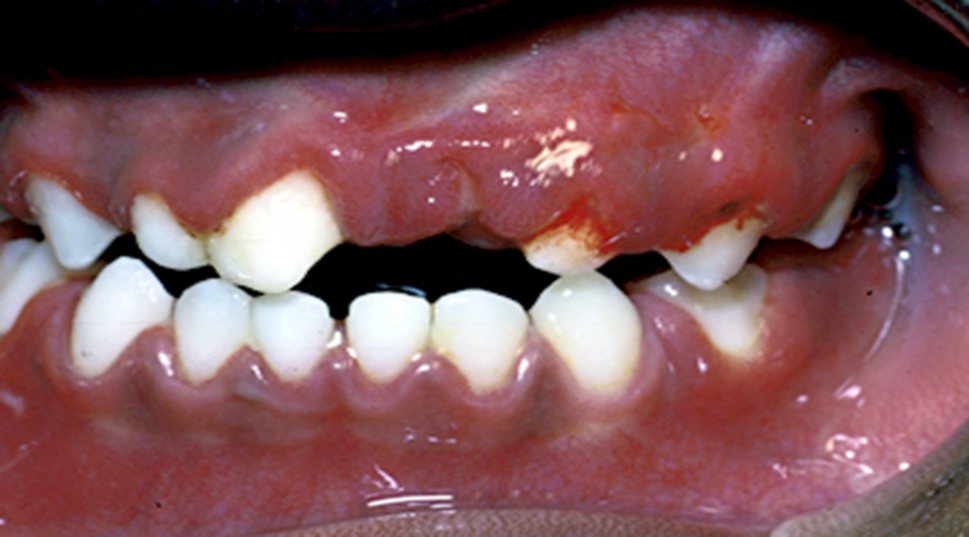

პირველადი მარტივი ჰერპესული გინგივოსტომატიტი – ეს არის მარტივი ჰერპეს ვირუსით დაინფიცირების შედეგი. პროდრომული ნიშნები – ცხელება, ანორექსია, გაღიზიანება, თავის ტკივილი წინ უძღვის პირის ღრუს ცვლილებებს. პირის ღრუში თავდაპირველად ვლინდება ღრძლების შეშუპება და ერითემა, ირგვლივ ვეზიკულების კლასტერებით. ღრძილები არის დაზიანებული და ადვილად სისხლმდენი (სურათი 9-ა). ვეზიკულების გასკდომის და ერთმანეთთან შერწყმის შემდეგ წარმოიქმნება ფართო მტკივნეული წყლულები, რომელიც შეიძლება ფუფხით დაიფაროს. ჩვეულებრივ ზიანდება ლოყის ლორწოვანი, ენა, ღრძილები, მაგარი სასა, ხახა, ტუჩები და პერიოლარური არე (სურათი 9-ბ). პაციენტს ასევე შეიძლება ჰქონდეს კანის დაზიანება, რომელიც ჩვეულებრივ ცალმხრივია, განსხვავებით ხფპდ -სგან, სადაც კანზე ცვლილებები ჩვეულებრივ ორმხრივია.

სურათი 9-ა